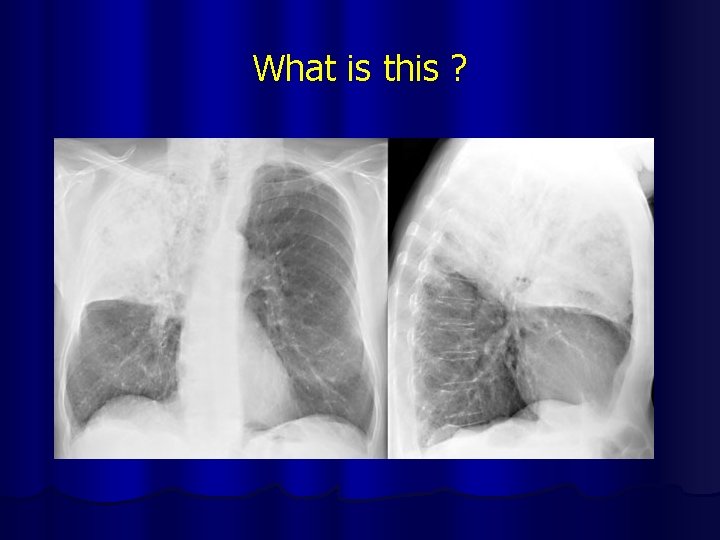

What is this ?

Pneumonia of RUL

Lobar Pneumonia of RUL

Segmental Pneumonia Right Upper lobe